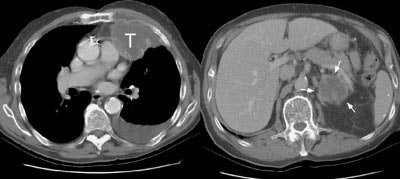

Example 1: This patient with non-small-cell lung cancer had a large necrotic primary tumor (T) and a large left adrenal metastasis (white arrows).

Example 2: In this patient with a T1N0 adenocarcinoma of the right lung, the staging CT scan revealed a heterogeneously enhancing mass in the left lobe of the liver (white arrows) and a low density mass in the left adrenal (yellow arrows). The liver lesion was subsequently shown to be an hemangioma and the adrenal lesion an adenoma. CT commonly detects other lesions which do not represent metastases, but which require further evaluation.

NOTE:  Click image to enlarge